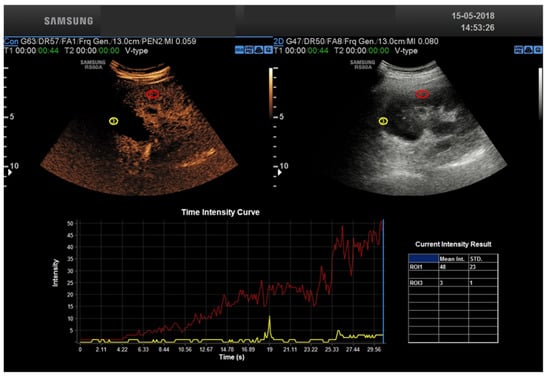

2.4. CEUS

2.5. CEUS Technique